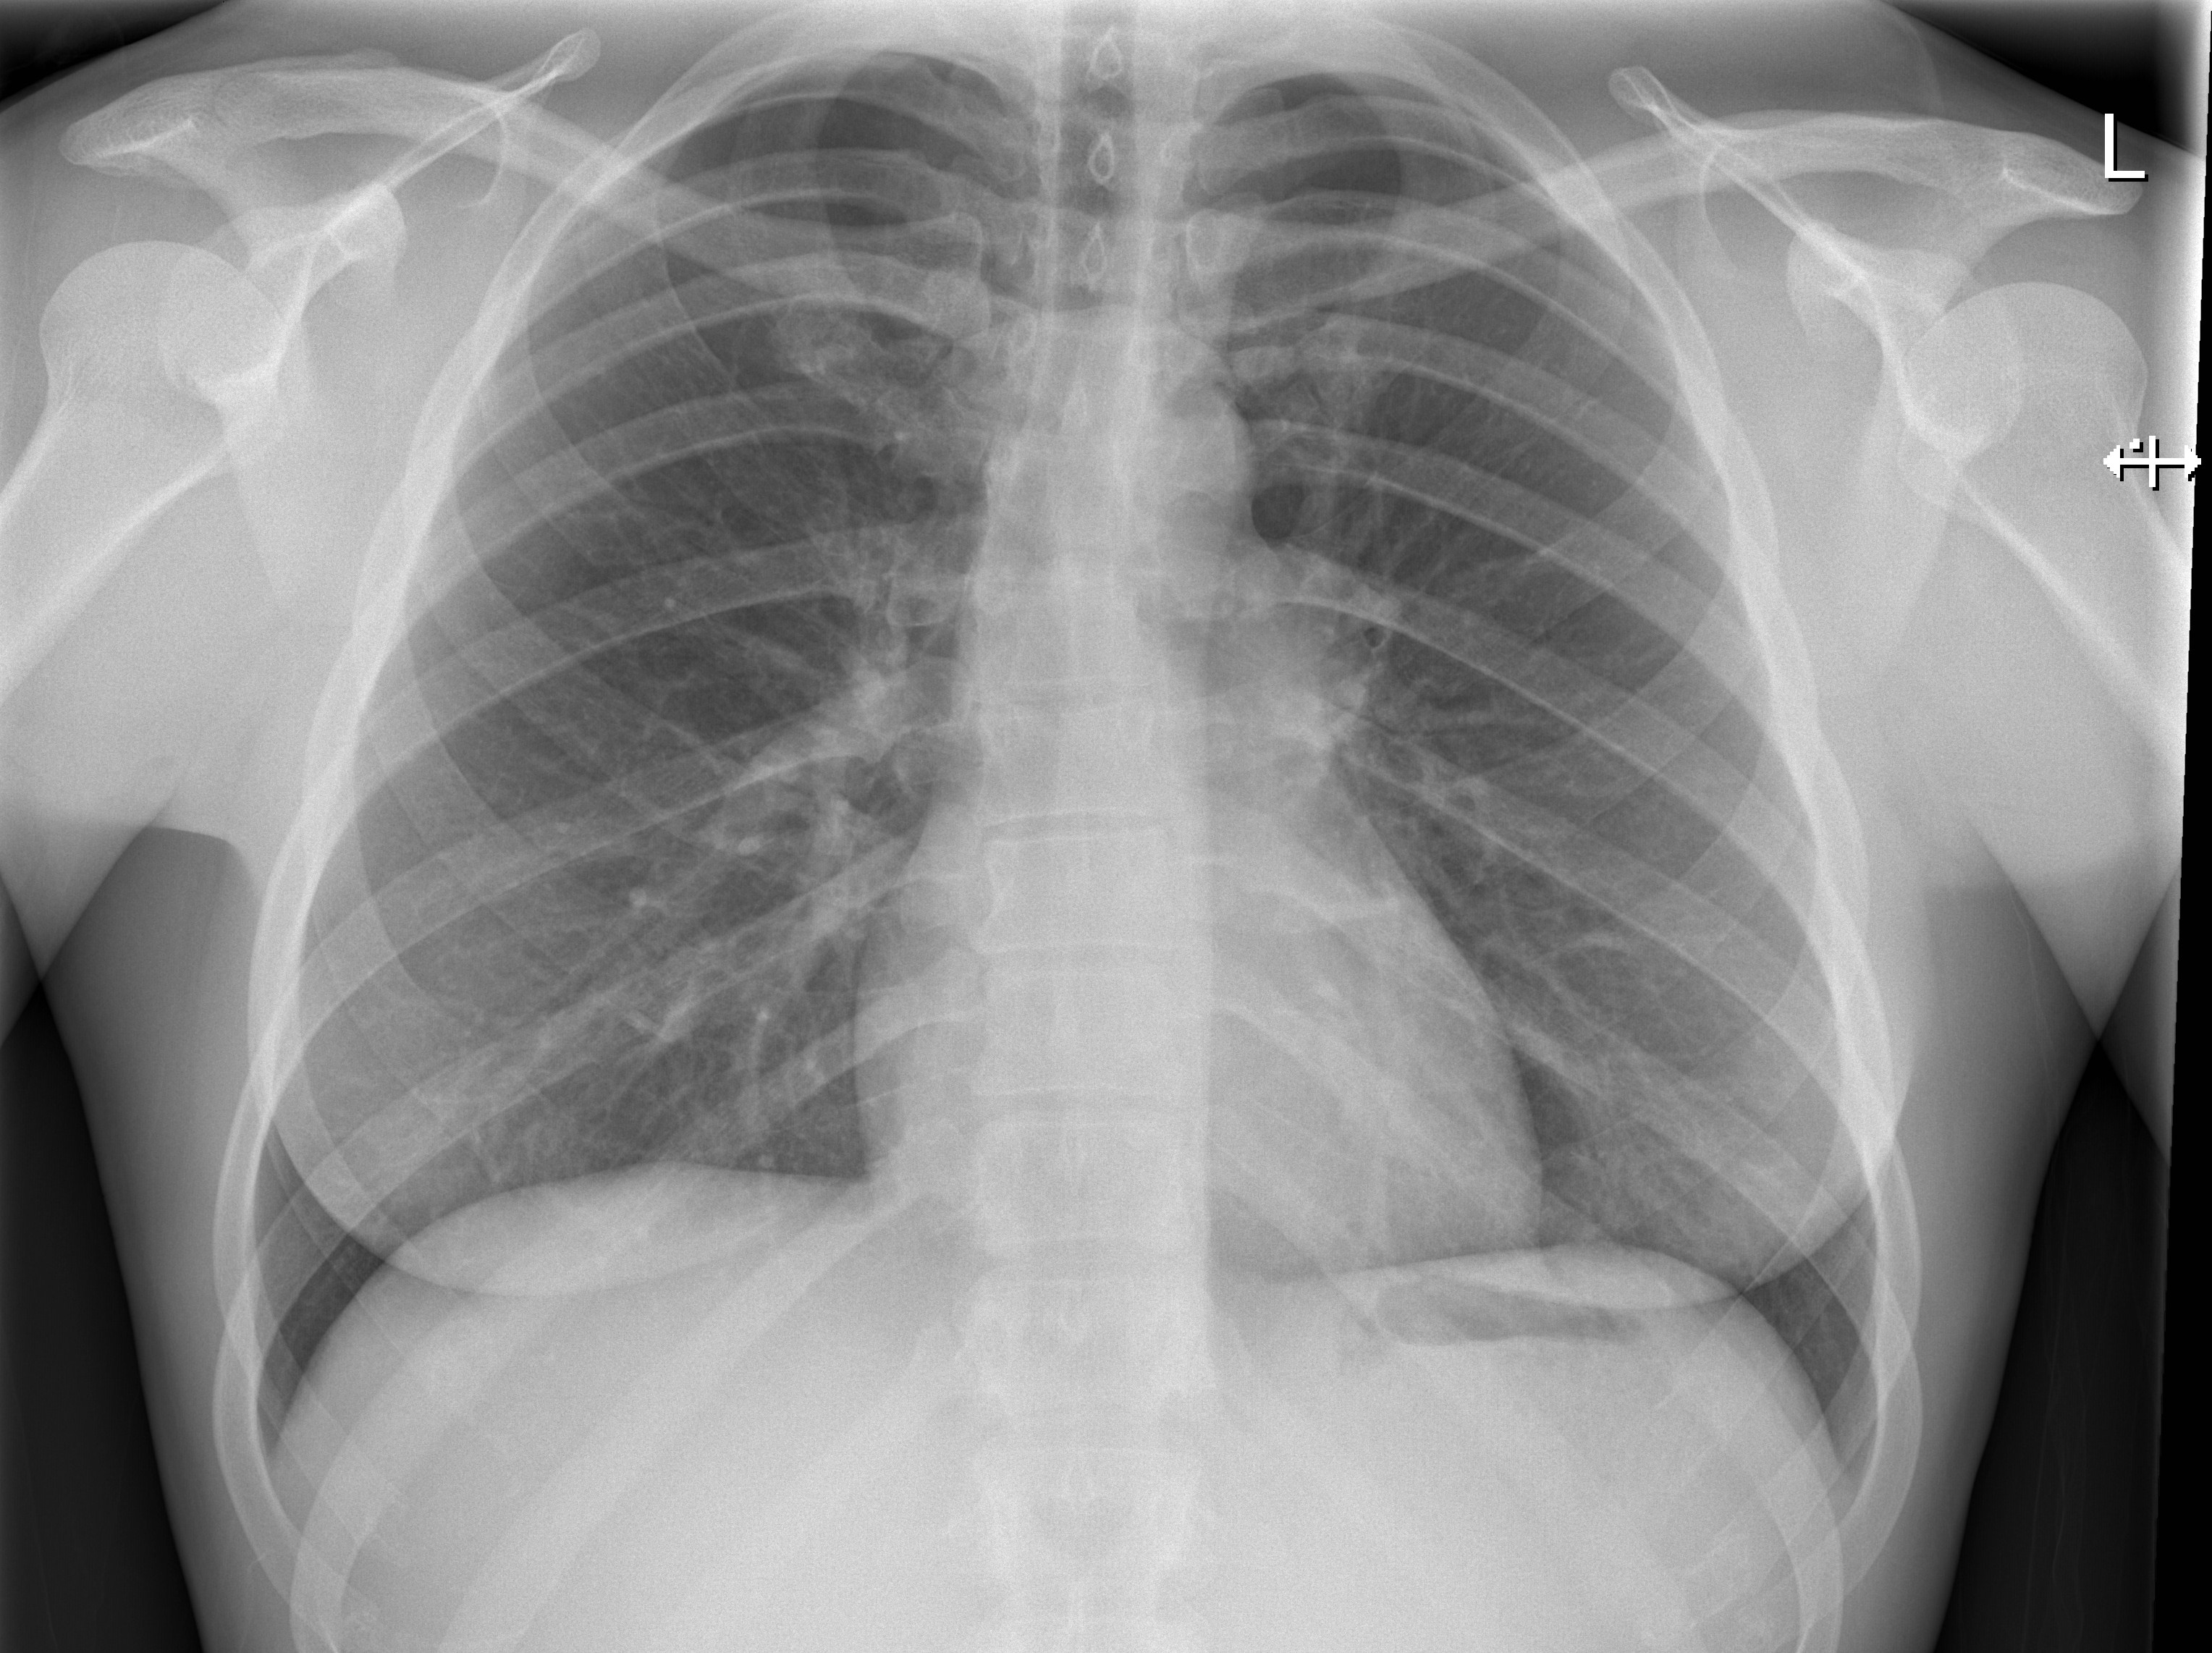

X-rays use invisible

electromagnetic energy beams to produce images

of internal tissues, bones, and organs on film

or digital media. Standard X-rays are performed

for many reasons, including diagnosing tumours or

bone injuries.

X-rays are made by using external radiation to

produce images of the body, its organs, and

other internal structures for diagnostic

purposes. X-rays pass through body structures

onto specially-treated plates (similar to camera

film) or digital media and a "negative" type

picture is made (the more solid a structure is,

the whiter it appears on the film).

When the body undergoes X-rays, different parts

of the body allow varying amounts of the X-ray

beams to pass through. The soft tissues in the

body (such as blood, skin, fat, and muscle)

allow most of the X-ray to pass through and

appear dark gray on the film or digital media. A

bone or a tumour, which is more dense than the

soft tissues, allows few of the X-rays to pass

through and appears white on the X-ray. At a

break in a bone, the X-ray beam passes through

the broken area and appears as a dark line in

the white bone.

Simple radiographs, such as a chest x-ray involve extremely low amounts of radiation. That means that the exposure to radiation is so small that the risk of any damage to cells in your body is very low. However, if you're pregnant or suspect that you may be pregnant, tell the radiographer beofre having the x-ray. The risk of most diagnostic x-rays to an unborn baby is small, your doctor may consider another imaging test in its place.